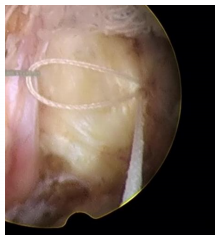

一次性纖維環(huán)縫合器的臨床應(yīng)用:

隨著纖維環(huán)縫合器縫合纖維環(huán)技術(shù)的推廣,很多學(xué)者做了相關(guān)的臨床研究。Parker等對(duì)30例纖維環(huán)縫合患者進(jìn)行了2年隨訪研究,零復(fù)發(fā)且椎間隙高度無(wú)改變。Bailey等通過對(duì)750名患者對(duì)比研究,發(fā)現(xiàn)纖維環(huán)非縫合組在術(shù)后2年時(shí)的再手術(shù)率較縫合組高45%。研究發(fā)現(xiàn),縫合纖維環(huán)可提高椎間盤生物力學(xué)性能,縮短其愈合時(shí)間,同時(shí)也減緩椎間盤組織的退變進(jìn)程。修復(fù)后纖維環(huán)回縮可減少對(duì)神經(jīng)根刺激,可有效消除疼痛癥狀。目前LDH髓核摘除術(shù)后復(fù)發(fā)的主要病因?yàn)槔w維環(huán)缺損、持續(xù)重復(fù)應(yīng)力因素等,比較明確的病因?yàn)槭中g(shù)導(dǎo)致的纖維環(huán)缺損,總結(jié)得出髓核突出少、纖維環(huán)缺損嚴(yán)重者術(shù)后的復(fù)發(fā)率高??p合后纖維細(xì)胞受到反復(fù)牽拉應(yīng)力刺激,可促進(jìn)纖維環(huán)的愈合和防止炎癥因子的產(chǎn)生。纖維環(huán)愈合產(chǎn)生的瘢痕組織可減輕關(guān)節(jié)突關(guān)節(jié)的應(yīng)力作用??p合纖維環(huán)可提高術(shù)后髓核“再水化”,促進(jìn)腰椎功能恢復(fù)。纖維環(huán)縫合益處:閉合裂口;降低術(shù)后復(fù)發(fā)率及再手術(shù)率;減輕髓核組織的免疫學(xué)反應(yīng)和炎癥介質(zhì)的外滲;有利于髓核的再生修復(fù)。要點(diǎn):切口大小以5mm的線形縱切口較佳,8mm以上需平行或交叉縫合2針;縫合針距離邊緣2~3mm為宜;縫合前,應(yīng)行邊緣探查,尋求無(wú)佳的縫合點(diǎn)。目前纖維環(huán)縫合面臨的重要問題是如何改善或降低縫合處的應(yīng)力積累,受應(yīng)力積累影響瘢痕組織及神經(jīng)纖維可能侵入椎間盤,可引起盤源性疼痛。有學(xué)者對(duì)比研究得出,單針簡(jiǎn)單縫合,可降低術(shù)后復(fù)發(fā)率,雙針交叉或平行縫合療效更好,而改良荷包縫合,術(shù)后能避免髓核再次突出,生物力學(xué)完整性可得到更好保留。